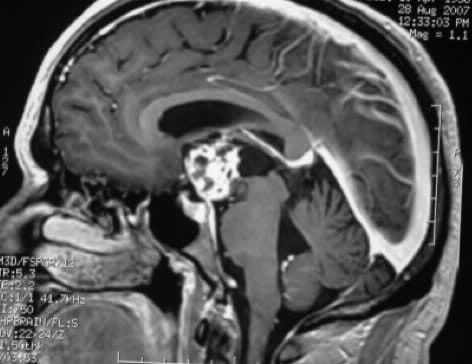

Adenoma secretante

El prolactinoma es el tipo más común de tumor hipofisario (adenoma) que produce una hormona. Representa aproximadamente el 30% de todos los adenomas de la hipófisis. Casi todos los tumores hipofisarios no son cancerosos (benignos). Un prolactinoma se puede presentar como parte de un trastorno hereditario llamado neoplasia endocrina múltiple tipo 1 (NEM 1).

Por lo menos la mitad de todos los prolactinomas son muy pequeños (menos de 1 centímetro o 3/8 de una pulgada de diámetro). Estos pequeños tumores ocurren con más frecuencia en las mujeres y son llamados microprolactinomas.

Los tumores más grandes son más comunes en los hombres. Tienden a ocurrir a una edad avanzada. El tumor puede crecer hasta un tamaño grande antes de que aparezcan los síntomas. Los tumores más grandes de 3/8 pulgadas (1cm) de diámetro son llamados macroprolactinomas.